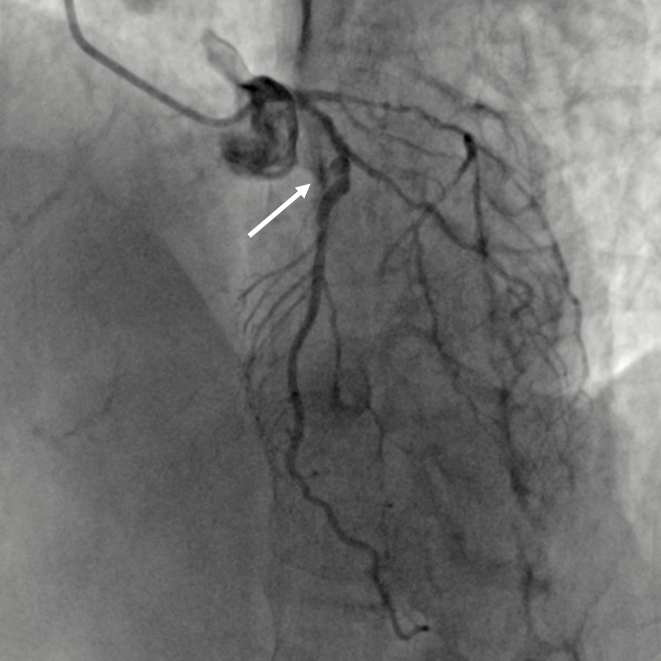

患者女,71岁,因“反复胸痛、胸闷4年余,加重”入院。患者入院诊断:冠心病不稳定心绞痛。入院完善相关检查后,患者2022年7月22日行冠脉造影提示:左主干无狭窄,前降支近段至中段90%狭窄伴钙化;回旋支近-中段弥漫性狭窄约70-90%;右冠近段至中段弥漫性狭窄约60-80%。拟对冠脉三支严重病变进行介入治疗。前降支近端至中段重度狭窄伴明显钙化。在使用2.5*15mm高压球囊,2.5*15mm切割球囊8-16atm反复预扩张后,仍无法充分扩张病变,考虑到前降支最重钙化病变处呈“小波浪”迂曲,行钙化病变旋磨术并发症风险较大,决定先完成左回旋支、右冠脉介入治疗后,择期再次对前降支严重钙化狭窄行介入治疗。

再次手术前,李浪团队根据患者冠脉病变特点制订了细致的手术计划。考虑到该患者此前手术未能成功原因:采用了高压球囊、切割球囊均未能充分扩张前降支严重钙化迂曲病变,判断该病变为较为严重的钙化病变。并且钙化病变血管迂曲,若采用旋磨技术,冠脉穿孔风险较大。因此,李浪教授团队决定采用目前最先进的冠脉钙化斑块碎裂术,即采用来解决该例病例的困局。通过先进的冠脉光学相干断层成像(OCT)与冠脉造影融合技术精准指导介入治疗,进一步准确评估冠脉病变钙化严重程度及病变特征,同时采用国内刚上市的Shockwave冲击波球囊方案,精准碎裂严重冠状动脉钙化斑块,使用OCT精准评估冠脉钙化斑块碎裂术效果,指导支架植入。